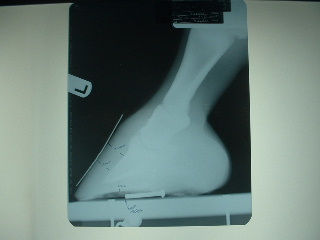

He's ouchy on the left front and very stiff in his hind end; vet came out yesterday and took xrays of his feet knowing that shoes will be put on.

He's been on weekly adequan for the last 4 weeks and he seemed to get worse... his right hind was shaking last week when I went to clean his foot. Vet thinks it may be because he only has 11mm of sole depth. He didn't block him, but did examine and watch him move and examined him again. No soft tissue issues, but very sensitive to hoof testers along the bars and the bulb of his heels. I did tell him that my farrier has not been working due to injury, so he's at 5 weeks now without a trim.

I'm afraid being barefoot is actually exacerbating his hind end arthritis and the vet said it's possible because he's loading the hind more to take weight off the front. I asked the vet if he thought I made a mistake by taking him barefoot and he said no. His hoof form is wonderful and to get to that with shoes would have taken MUCH longer. He does not believe navicular is an issue any longer as long as his hoof form stays correct.

The good news: we've fixed the front feet, he believes that putting on Epona shoes on the front will help a lot and that I will be able to ride/show him this year.

I think he looks really good but he's telling us something different. On the xrays, you'll see a nail on the bottom, the tip of the nail is the tip of his frog. Vet said the toe could come way back:

Left front:

Right front:

They look good Aileen and especially have improved a bit in the run under heels, a difficult and slow correction to be sure. I do not see a lot of room to back the toe further in the images though break over could be moved back a touch. I might feel different after actually examining the feet.